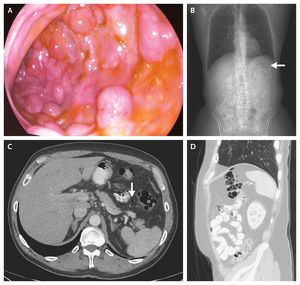

A 63-year-old man presented for a screening colonoscopy. During the colonoscopy, several submucosal polypoid lesions, 3 to 8 mm in diameter, were noted in the splenic flexure. Since the lesions were easily indented with gentle pressure and had a bluish hue, pneumatosis intestinalis was suspected (Panel A). When the lesions were punctured, they became deflated, supporting the diagnosis (see video). Computed tomography revealed multiple air pockets in the intestinal wall at the splenic flexure (Panel B, arrow; Panel C, asterisk; and Panel D) and some free intraperitoneal air (Panel C, arrow). The results of histopathological inspection of an endoscopic-biopsy specimen were consistent with pneumatosis intestinalis. Pneumatosis intestinalis is diagnosed by the presence of air pockets in the intestinal wall. In certain cases, pneumatosis intestinalis may be considered a surrogate marker for intestinal ischemia and impending perforation. However, the condition may also occur in a benign context and is no longer considered a disease but rather a sign, and its significance needs to be considered in accordance with each patient's clinical context. This patient required no specific treatment and has remained asymptomatic. Tomer Adar, M.D. Kalman Paz, M.D. Digestive Diseases Institute, Shaare Zedek Medical Center, Jerusalem, Israel source: nejm.org